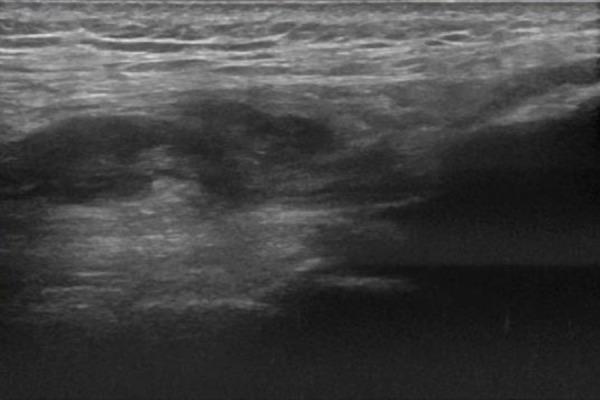

We present a rare case of bilateral QTR with a simultaneous Achilles Tendon Rupture involving a 31 years old Caucasian man who is a semi-professional body builder taking anabolic steroids. To date bilateral QTR with additional TA rupture has only been reported once in the literature and to our knowledge this is the first reported case of bilateral QTR and simultaneous TA rupture in a young, fit and healthy individual.

我们呈现了一例罕见的双侧股四头肌肌腱断裂合并跟腱同时断裂的病例,患者为一名31岁的白种男性,是一名服用合成代谢类固醇的半职业健美运动员。迄今为止,双侧股四头肌肌腱断裂合并胫前肌断裂仅在文献中被报道过一次,据我们所知,这是首例在年轻、健康且体格健壮的个体中发生的双侧股四头肌肌腱断裂及胫前肌同时断裂的病例。